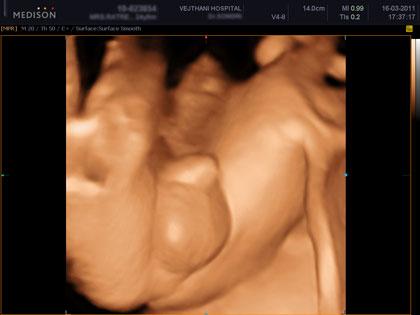

อัลตราซาวด์ 4 มิติ คือการอัลตราซาวด์ 4 มิติ ส่วนใหญ่ก็จะใช้ดูโครงสร้างของเด็ก ดูความผิดปกติ รวมทั้งสามารถดูสีหน้าท่าทางของทารก ซึ่งเป็นอาการตามธรรมชาติของทารก นอกจากนี้ก็ยังสามารถดูโรคที่เป็นความพิการทางโครงสร้าง เช่น ปากแหว่งเพดานโหว่ หัวใจพิการอย่างรุนแรง กะโหลกศีรษะ เป็นต้น ไม่ว่าจะเป็นอวัยวะภายนอกหรือภายใน ก็สามารถดูได้ทั่วทั้งร่างกายของทารก รวมไปถึงการตรวจวัดขนาดของทารก ทั้งนี้จะเป็นประโยชน์อย่างมากกรณีที่พบว่าทารกมีความผิดปกติ แพทย์สามารถวางแผนการรักษาหลังคลอดได้ล่วงหน้า ว่าจะรักษาอย่างไรต่อไป ซึ่งจะทำให้ทารกได้รบการรักษาในทันที

คลิปภาพทารกจากอัลตราซาวด์ 4 มิติ